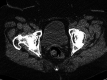

A known consequence of portal hypertension is the development of varices, which are described as "ectopic" when located at unusual sites in the abdomen. Ectopic varices carry a mortality rate as high as 40% after initial hemorrhagic episode. We report a patient who presented with hematuria secondary to bladder varices as the presenting symptom for a new diagnosis of cirrhosis. Cross-sectional imaging, early recognition of this rare event, combined with multidisciplinary management was essential for this patient to have a successful outcome.